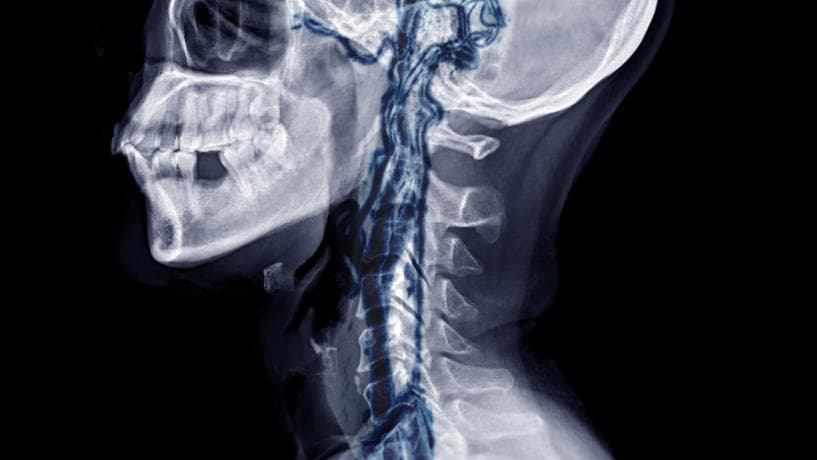

群発頭痛のメカニズム(西洋医学的視点)

医学的には、以下が関係していると考えられています:

- 内頚動脈の拡張

- 自律神経系の乱れ

- 三叉神経の過敏化

これらの異常な反応が連動し、片側の眼の奥に強烈な痛みを引き起こします。